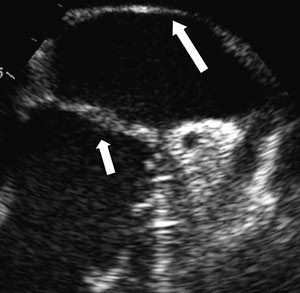

I tillegg til utredning med tradisjonelle ekkokardiografiske metoder ble pasienten også utredet med transtorakal tredimensjonal ekkokardiografi (fig 4), siden det nylig er rapportert at denne metoden kan erstatte transøsofageal ekkokardiografi i slike tilfeller.

Transtorakal tredimensjonal ekkokardiografi (3DE) har foreløpig liten utbredelse i klinisk sammenheng. Den seneste utviklingen innen transduserteknologi med muligheter for opptak i sanntid har forenklet og forbedret avbildningsprosessen betydelig (4). En av fordelene med 3DE-undersøkelse sammenliknet med transøsofageal ekkokardiografi er mindre ubehag for pasienten. I tillegg vil det gi en bedre kartlegging av de anatomiske strukturene, noe som er viktig dersom det blir nødvendig med kirurgisk behandling. Det er nemlig en betydelig utfordring å danne seg et godt tredimensjonalt bilde av strukturer inne i kroppen ut fra todimensjonale bilder. Nytten av tredimensjonale fremstillinger er naturligvis betinget av god bildekvalitet. Fra et apikalt vindu vil bildekvaliteten for strukturer i atriet begrenses av stor avstand fra lydhodet (proben). Fra et parasternalt vindu er god fremstilling av atriestrukturer, som en slik membran, også avhengig av en gunstig vinkel mellom lydbølgene og membranen. Hos denne pasienten var det parasternale vinduet best egnet til å fremstille membranen.